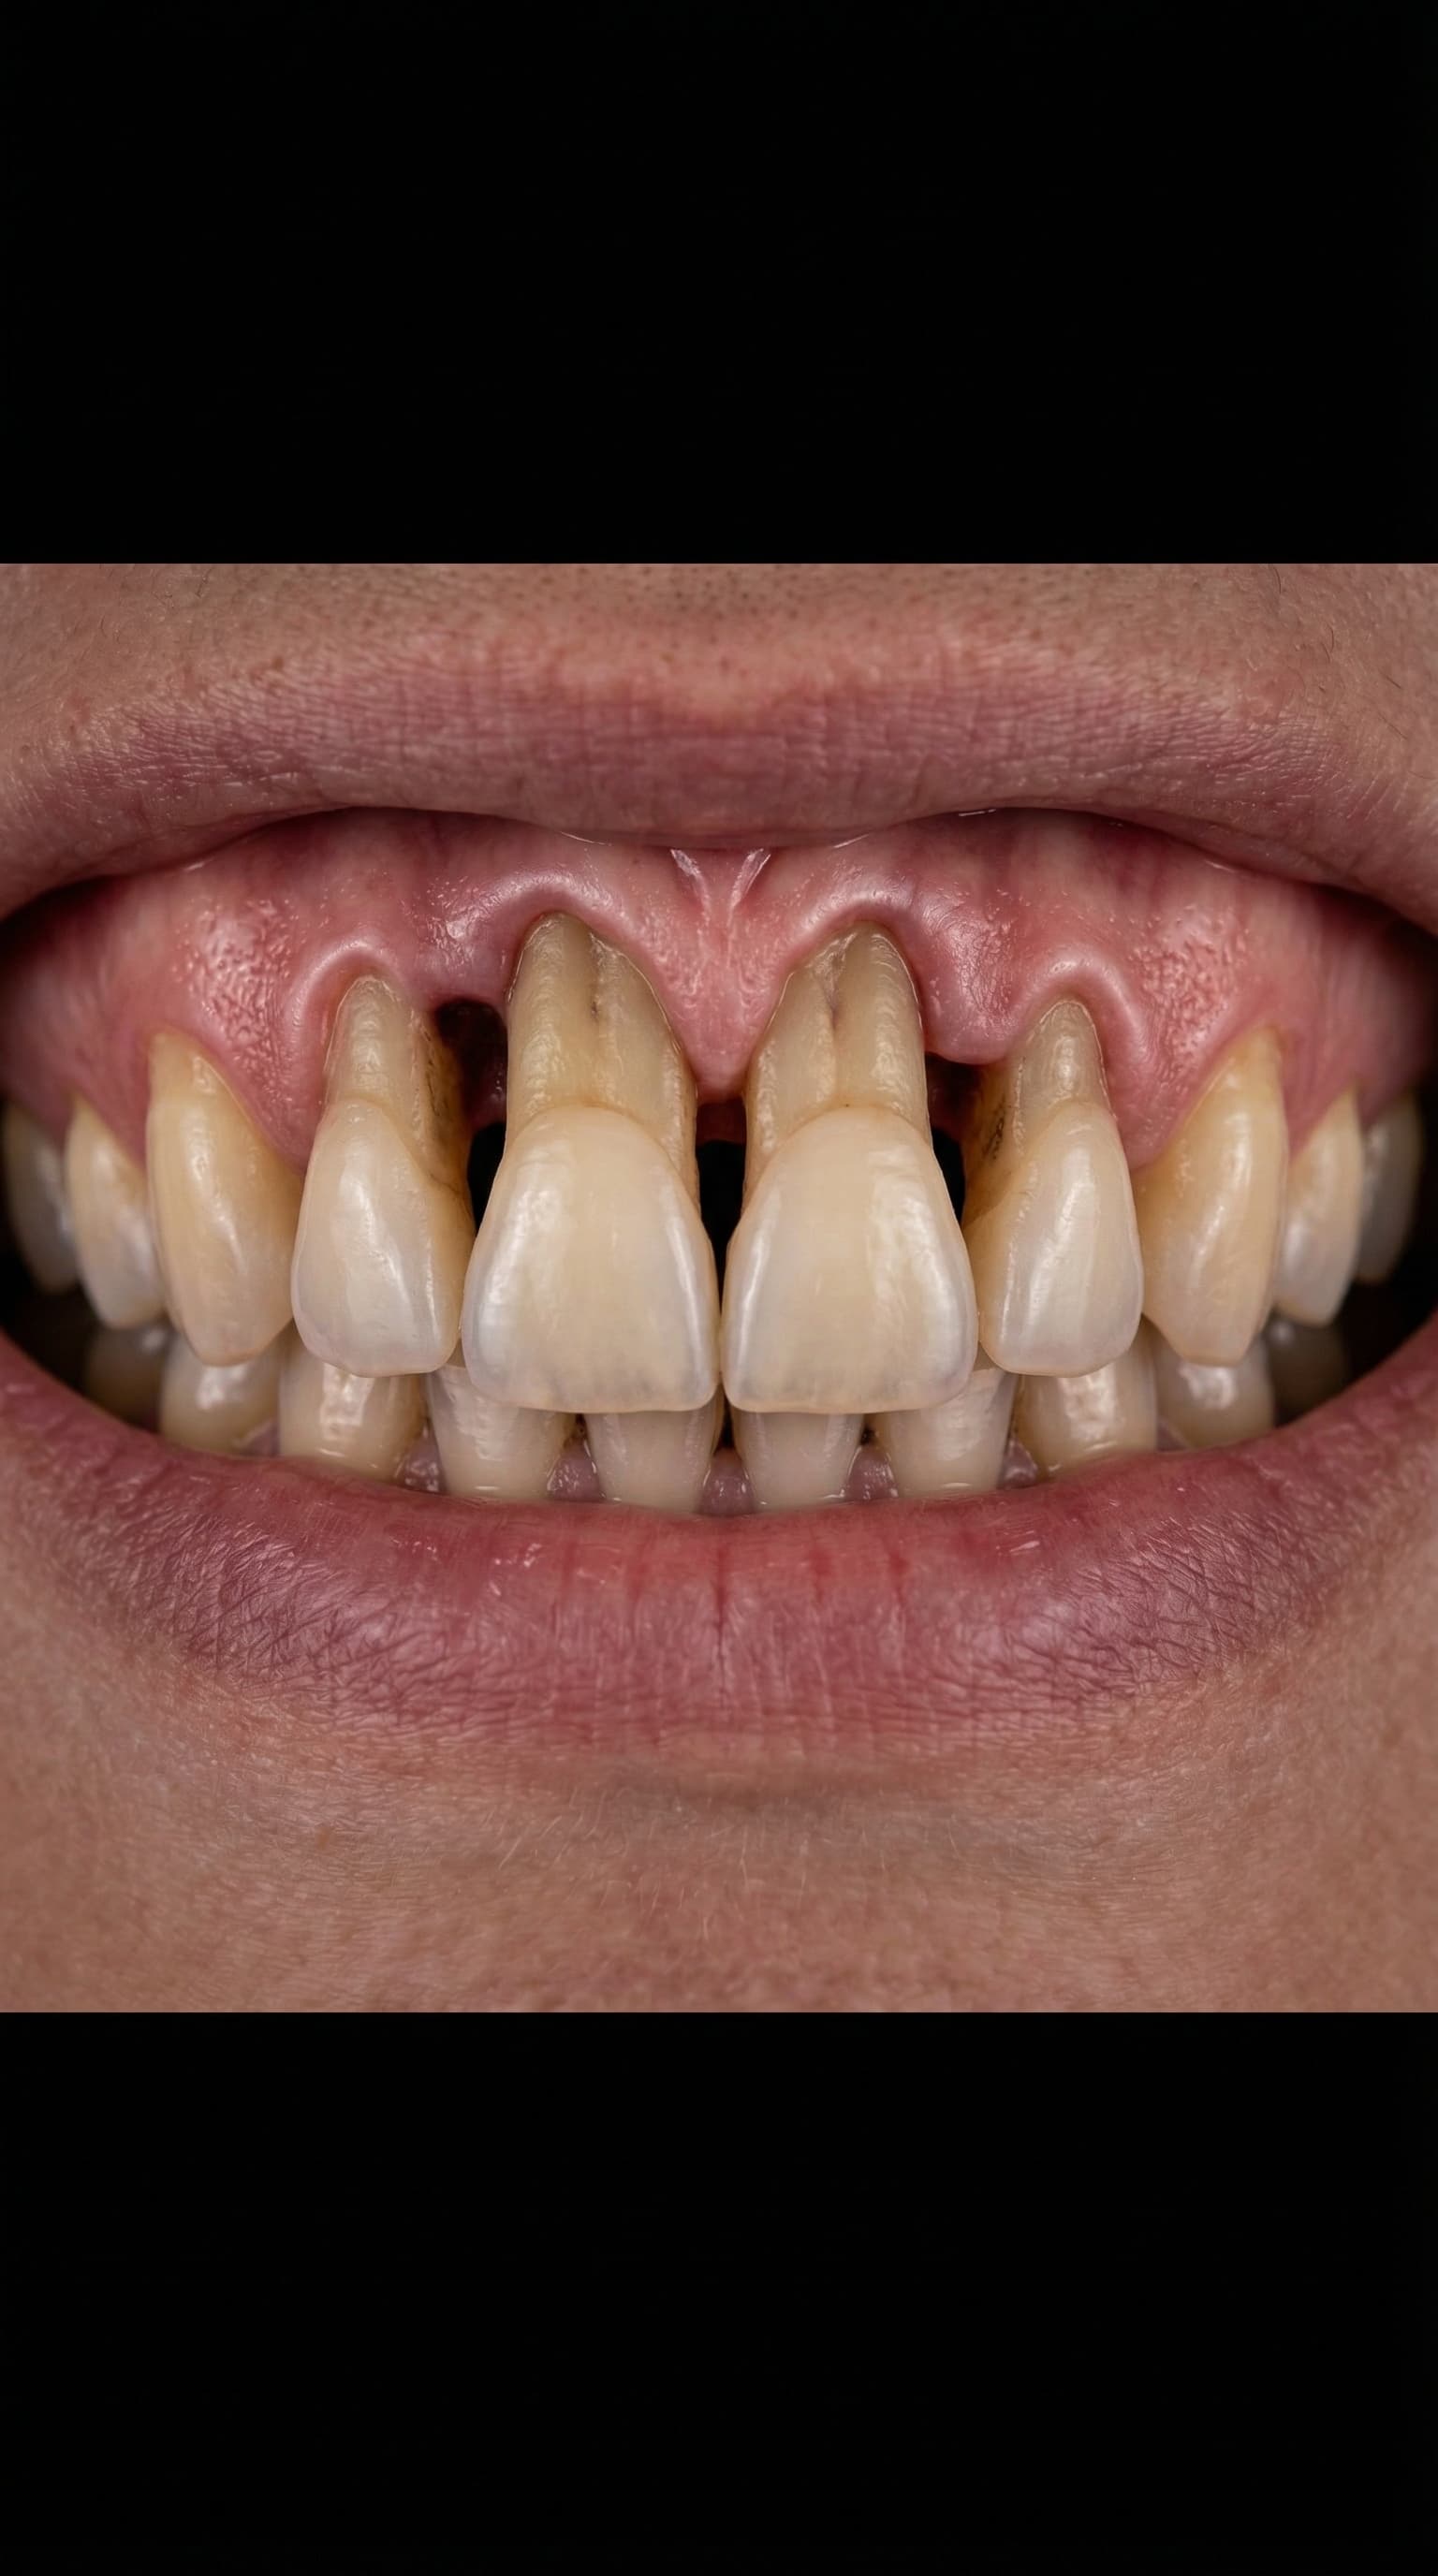

Full Arch Transformation

Watch a complete All-on-4 dental implant journey — from damaged teeth to a brand new smile. Every step performed by Dr. Antipov at our Roseville office.

Severely worn and damaged upper teeth — patient unable to eat or smile comfortably